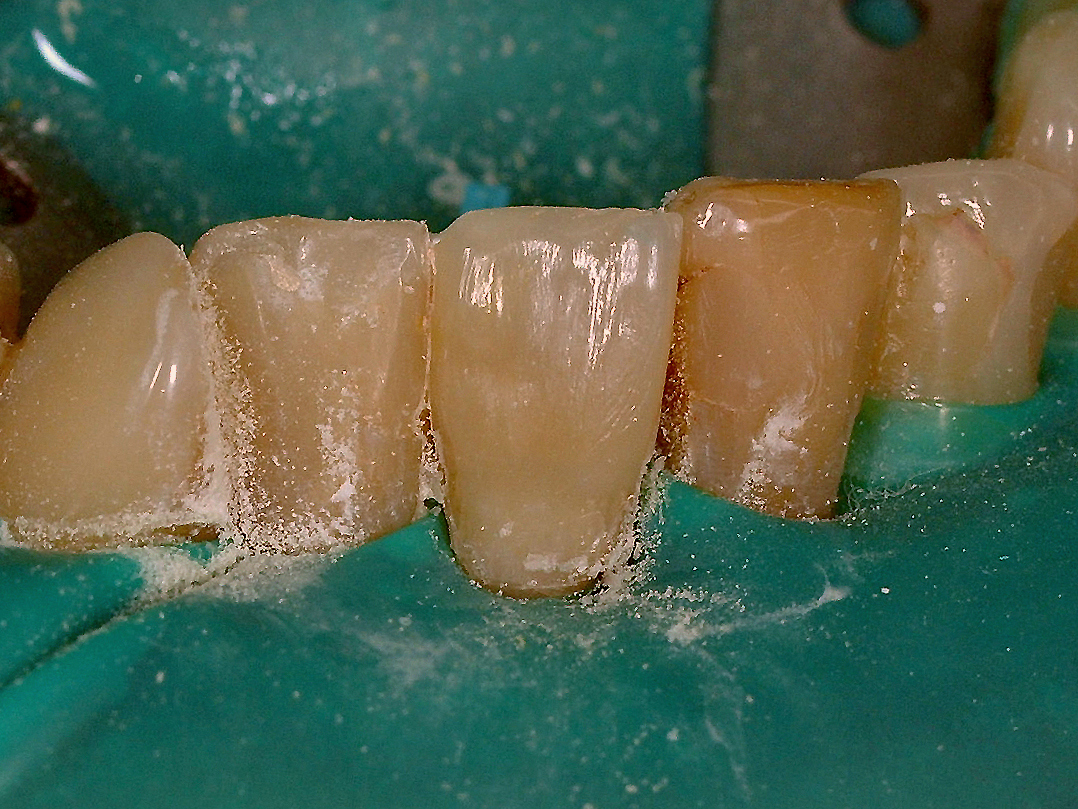

Pacjent zgłosił się, by dokonać korekty wyglądu siekaczy żuchwy. Zaplanowano odbudowę na wkładzie zęba 41 i licówkę na zębie 31. Zabieg przeprowadzono z zastosowaniem wkładu systemu RalyX Fiber Post i materiału Filtek Supreme XT.